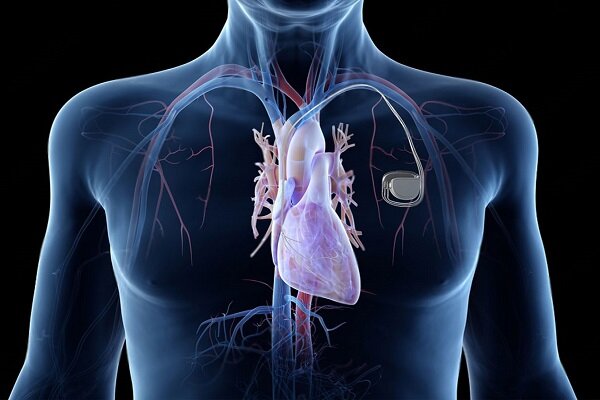

استرس باعث بیماری قلبی میشود

استرسهای طولانیمدت علاوه بر تأثیرات روانی، میتوانند سلامت قلب و عروق را نیز تحت تأثیر قرار دهند و در صورت تداوم، زمینه ساز افزایش فشارخون و بروز بیماریهای قلبی شوند.